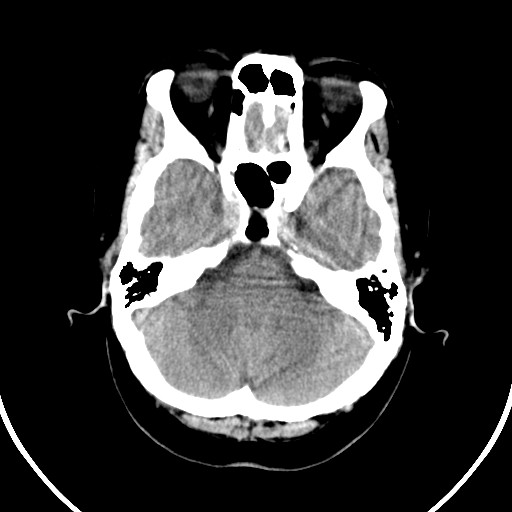

标题: CT21850:女,56岁,右中指淤肿,右手麻痹1天

女,56岁,右中指淤肿,右手麻痹1天

右侧侧脑室旁脑白质腔隙性脑梗死。

右侧基底节多发小梗塞

右基底结区腔梗

右侧基底节区腔隙性脑梗塞

右侧基底节多发腔梗!

双侧侧脑室额角旁对称性略低密度影,边缘模糊,无占位效应,考虑轻度脑白质稀疏症(病人有高血压吗).,右枕叶低密度影多为伪影,不放心薄扫一下.

考虑脑白质病。

考虑脑白质病

右枕叶条状低密度影不应该忽略可能极具意义